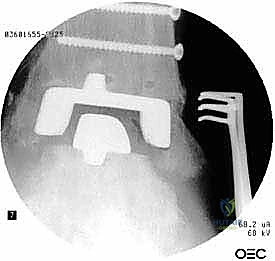

مراجعة مفصل الكاحل الصناعي هي إجراء جراحي ضروري لمعالجة المشاكل التي قد تنشأ بعد الجراحة الأولية، مثل كسور الكعبين أو عدم استقرار المفصل. يتضمن العلاج التشخيص الدقيق عبر الأشعة السينية والتصوير المقطعي، يليه التدخل الجراحي لتثبيت الكسور واستعادة وظيفة الكاحل، مع التركيز على التعافي المبكر.

- الأشعة السينية مع تحميل الوزن (Weight-bearing X-rays): لتقييم الزوايا الميكانيكية وتحديد مدى هبوط المفصل أو وجود كسور في الكعب.

الخطوة الخامسة: تركيب المفصل الجديد أو الدمج

يتم إدخال المفصل الجديد المخصص للمراجعة، والذي يحتوي غالباً على سيقان (Stems) تدخل عميقاً في عظمة الساق وعظمة الكاحل لضمان الثبات الميكانيكي. في حال وجود كسور في الكعب، يتم تثبيتها في هذه المرحلة.